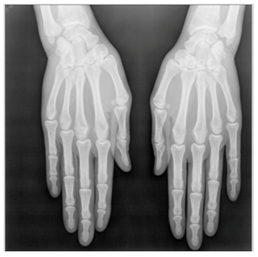

In this section, we present and analyze the results obtained with the proposed method, and compare it to methods proposed in similar works. The proposed watermarking system is implemented using MATLAB and executed on a Windows machine with the following characteristics: Intel R Core i5 processor, 4 GHz, 4 GB RAM, and Microsoft Windows 8 Professional operating system platform. In our experiments, we have used DICOM images of size 512 × 512 pixels as shown in Table 1.

Table 1.

Original images.

In our method, several copies of the watermark are embedded in the RONI region, and the ROI region is kept intact. ROI and RONI are separated using the method presented in Section 3.2. The watermark is inserted in the RONI using a linear interpolation technique. From the results, one can see that there is no significant visual difference between the original and the watermarked images. Nevertheless, the difference appears through the values of SSIM and PSNR presented in next subsection.